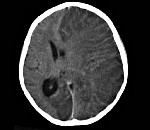

Патогномоничным томографическим признаком, характеризующим энцефалит Расмуссена, выступает прогрессирующая церебральная гемиатрофия. Как правило, вначале регистрируется увеличивающееся с течением времени расширение сильвиевой щели, затем отмечаются атрофические изменения конвекситальных отделов церебральной коры. При наблюдении в динамике типично увеличение зоны корковой атрофии наподобие растекания масляного пятна по пергаменту.